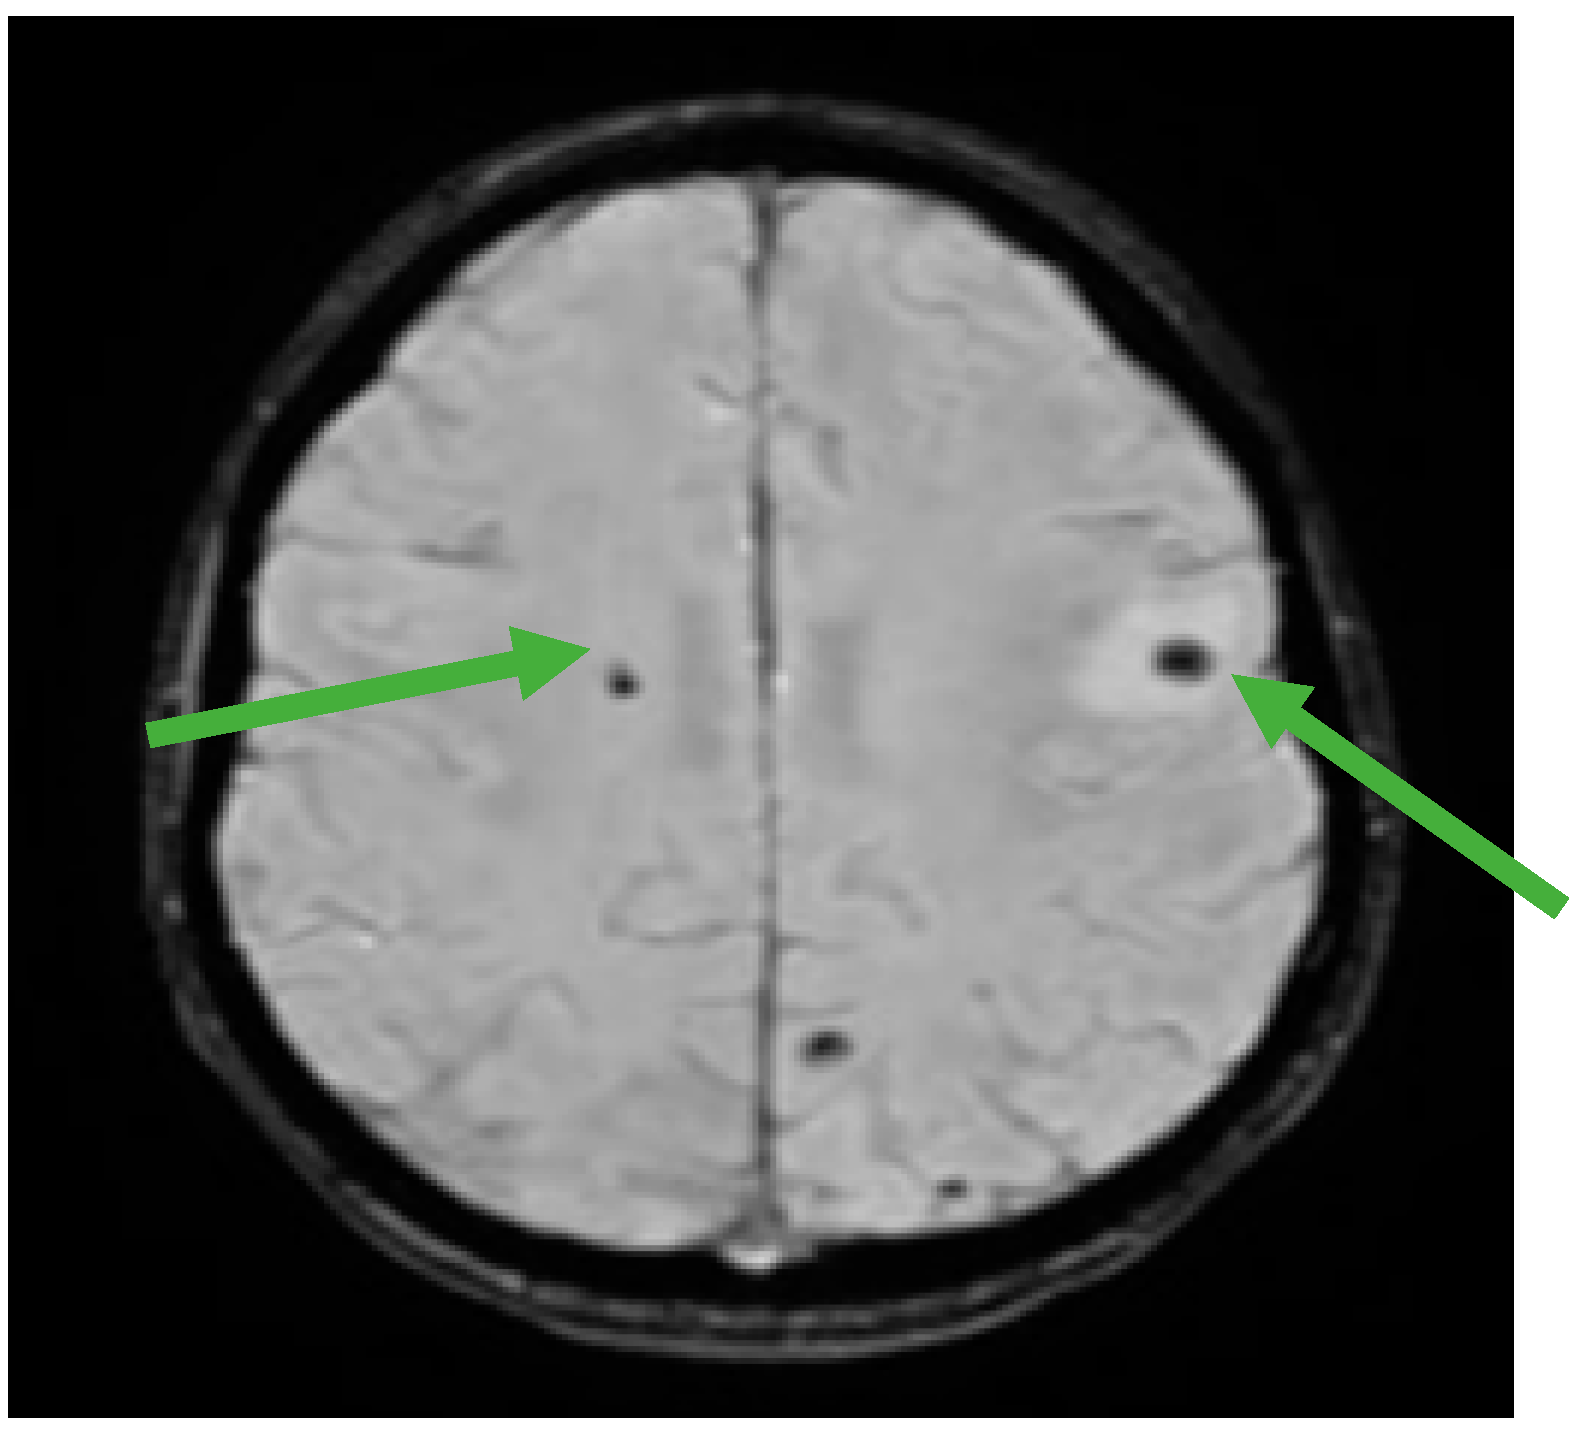

Figure 5.

Brain MRI showing multiple hemorrhagic metastases at the supratentorial and cerebellar level (green arrows).